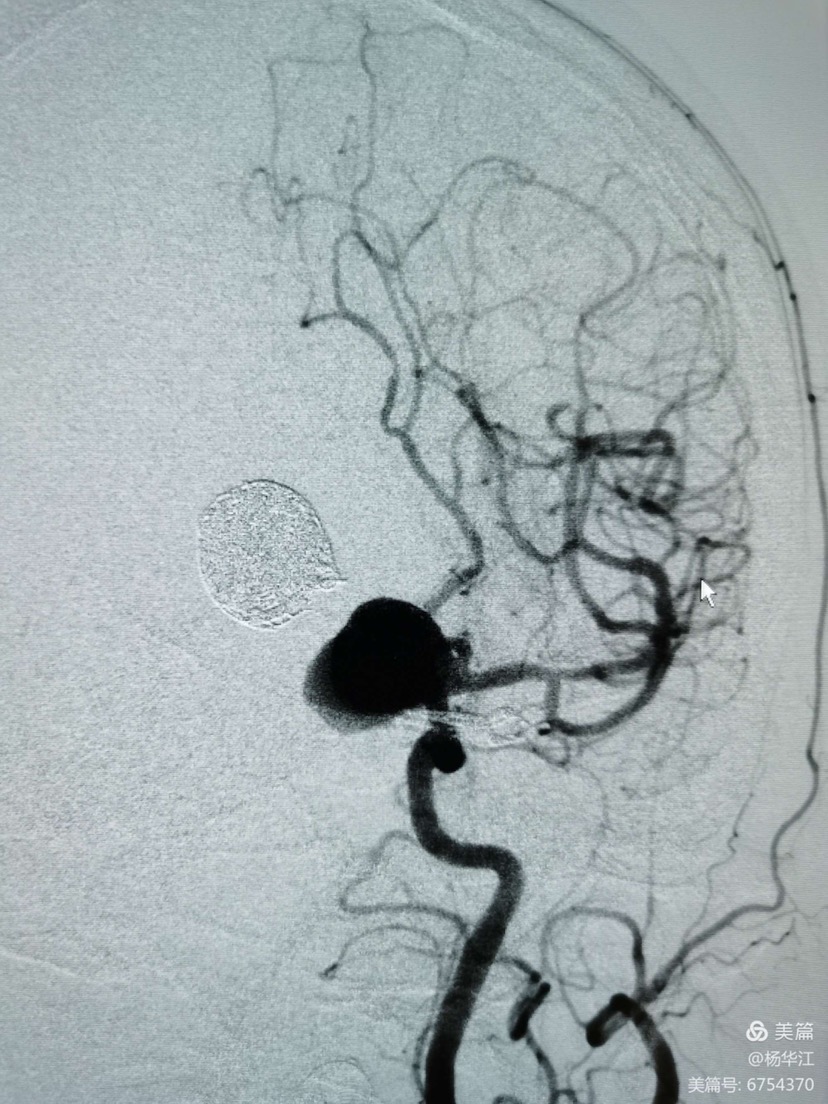

术中先行后循环造影显示:动脉瘤几乎完全不显影,各分支显影良好。这个效果还是有些出乎我们的意料的好,大概率消除了迟发性出血这个隐患。

这是我们用了10年之久西门子机器做出的3D后处理影像,还行吧,尽管稍有些失真。